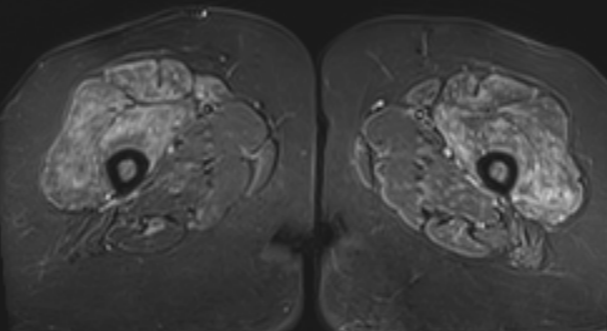

3. Myositis